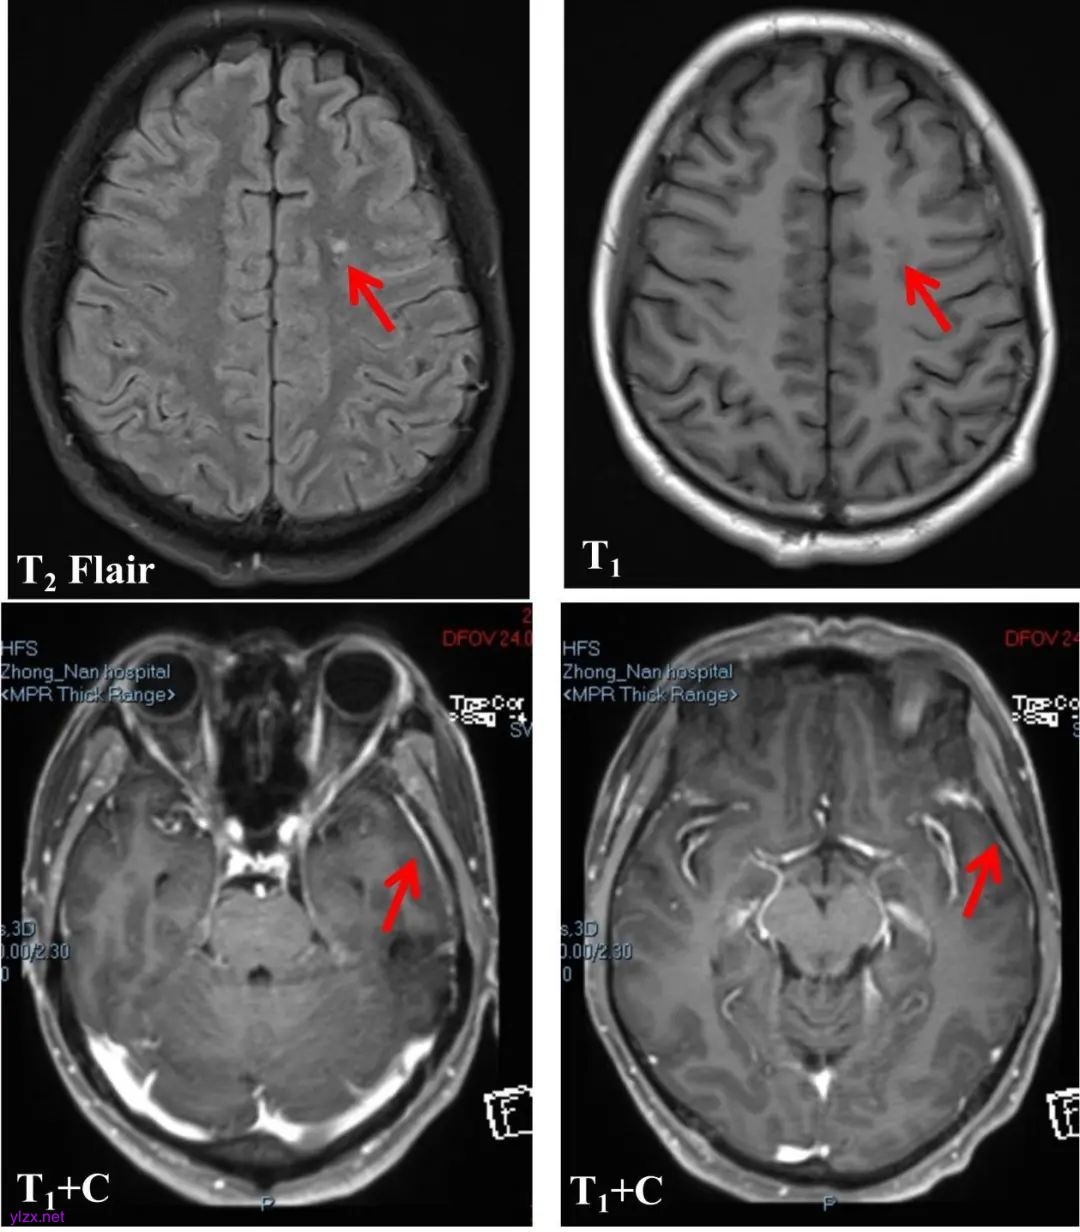

患者男,50岁,因“情绪低落3个月,头痛1个月,记忆力减退半月”于2023年6月22日入院。3个月前因工作情绪低落,1个月前无明显诱因出现双侧颞部剧烈头痛,数字疼痛评分量表(numerical rating scale,NRS)自评8分。2 d后头痛症状自行缓解,后进食少。半月前再次因压力事件出现记忆力下降,言行异常,前往当地医院2023年06月21日腰穿示脑脊液(cerebrospinal fluid, CSF)总蛋白1388.51 mg/L↑,细胞总数1.084×109/L↑。起病来,患者精神一般,食欲差,睡眠一般,体力下降,近1个月体质量下降十几斤。既往有长期间断头痛病史十余年。入院神经科查体:神清,双侧额纹对称,双侧瞳孔等大等圆,直径3.0 mm,对光反射存在,双眼外展稍受限,眼震可疑(+),左侧鼻唇沟较浅,口角向右歪斜,伸舌正常,精神紧张,言语稍含糊,语速较慢,理解力、时间地点定向力、近事记忆下降,计算力下降(如:100-7=107)。颈无抵抗,四肢肌力5级,左上肢肌张力稍高,余肢体肌张力正常;可见双上肢姿势性震颤,双上肢腱反射亢进。四肢深浅感觉粗查正常,病理征未引出,脑膜刺激征阴性,共济运动欠稳准。实验室检查:嗜酸性粒细胞百分比12.7%↑,嗜酸性粒细胞绝对值0.73×109/L↑(图1A)。感染性及血管性疾病筛查指标、寄生虫卵镜检、血+CSF寄生虫抗体和自身免疫性脑炎抗体(TBA+CBA)、CSF宏基因组病原学检测(DNA)均正常。CSF嗜酸性粒细胞百分比46%(图1B),寡克隆区带(+)。CSF蛋白1.34 g/L↑,有核细胞数45个/μL(嗜酸性粒细胞百分比为46%)。EEG:双侧额颞区可见多量中幅1.5~2 Hz慢波活动或节律,左侧颞区明显,可见左侧颞区间断δ节律。MMSE:10分。骨髓细胞检查提示三系增生伴粒系感染改变,嗜酸性细胞易见(图1C)。流式提示嗜酸性粒细胞(p9)占有核细胞4.8%。颅脑MRI检查示双侧侧脑室旁白质区见多发点状T2 Flair高信号灶,Fazekas 1级;增强扫描可见左侧颞区可疑硬脑膜强化(图2),考虑为嗜酸性粒细胞增多性脑膜脑炎。给予糖皮质激素(甲泼尼龙80 mg/d,5 d→泼尼松60 mg)、改善认知(多奈哌齐10 mg/d)、控制大脑皮层异常放电及稳定心境治疗(丙戊酸钠250 mg/12 h)。使用糖皮质激素治疗后,患者精神紧张较前明显减轻,时间地点定向力、计算力明显好转。2023年7月3日复查CSF生化:蛋白0.73 g/L↑;CSF常规:有核细胞总数15个/μL↑,未见嗜酸性粒细胞。复查外周血嗜酸性粒细胞百分比及绝对值较前明显下降。院外口服糖皮质激素治疗,泼尼松每2周减少5 mg缓慢减至停药。1个月后患者前往门诊复诊,MMSE检查30分,复查血常规嗜酸性粒细胞正常。3个月后住院复查CSF蛋白0.44 g/L↑、嗜酸性粒细胞数0.20×109/L(4.5%),EEG示轻度异常,未予特殊治疗出院。

Fig.2 Cranial MRI findings

图2 颅脑MRI检查结果 双侧侧脑室旁白质区见多发点状T2 Flair高信号灶,增强可见左侧颞区硬脑膜强化。